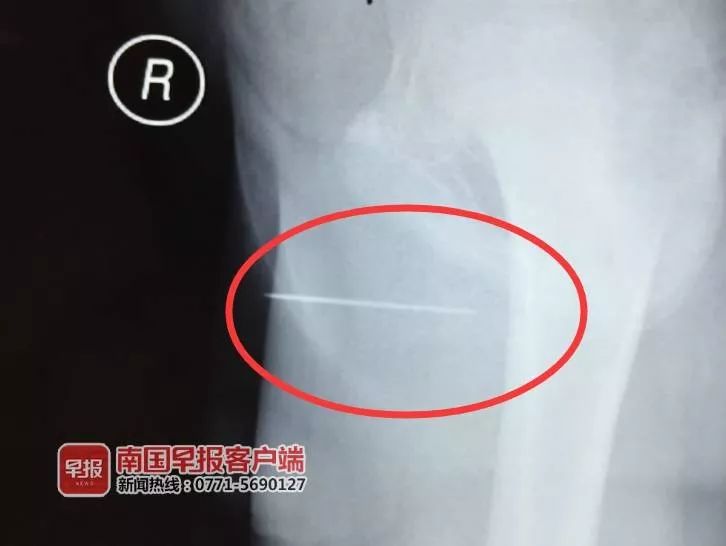

经过拍片,确认小李的*体下**内有一根长约数厘米的异物。为进一步治疗,6月17日,小李被转至北海市人民医院。据该院泌尿外科主任医师陈奎介绍,小李*体下**内的异物是一根细长的金属铁丝。异物进入后,小李出现尿道疼痛、尿痛等症状,还有少许的血尿。

陈奎告诉记者,根据X光片检查结果显示,金属铁丝的两头都已插进了小李尿道的软组织内,所幸其膀胱黏膜未见异常。经过科室会诊,陈奎决定通过微创手术将针取出。